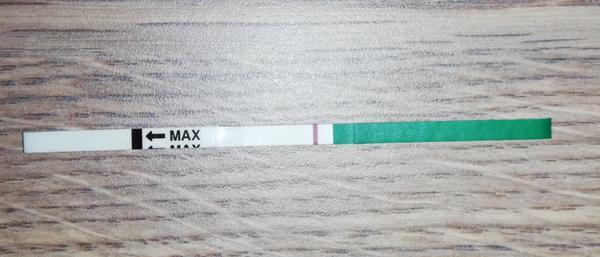

Duch na teste

ahojte babule, mam taku otazku...mate skusenost ze pocas 3 dni vam nesilnela druha ciarka na teste ale bola rovnaka???ako duch????

@popuska aj ja vidim 🙂 drzim prsty nech silnie kazdym dnom ❤

@123vika krasne silneju ❤

Vsetkym Vam drzim prsty nech Vam tie ciarocky silneju 👍😍